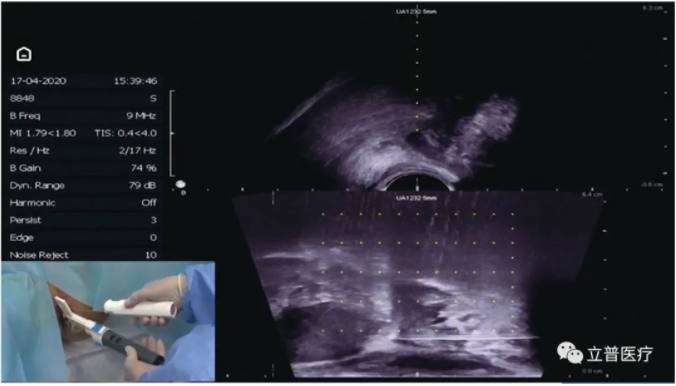

立普医疗推出了全系列的经会阴活检解决方案,适配的超声探头有:BK 8818,BK 8848,日立U533,百胜 TRT 33 等探头机型,并有通用型架体可以适配其他超声探头,基本覆盖了现有市场上的经会阴型探头。

拥有多项专利的架体可以适应经会阴穿刺的需求,只需要旋转架体,就可以全方位地进行穿刺。有引导线型的机型还可以进行引导线匹配,更加精准快速地达到穿刺所需位置。